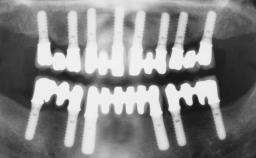

Graduated from the University of Zurich, Switzerland. He has been a visiting assistant professor at University of British Columbia (Canada) and Harvard University. From 1983-2012 he was Professor and Chairman of the Department of Fixed Prosthodontics and Occlusion at the University of Geneva School of Dental Medicine and President of the School of Dental Medicine in Geneva from 2005 to 2009. He is currently Guest Professor in the Department of Oral Surgery and Stomatology, University of Bern.

Academy content by Urs Belser (16 items)